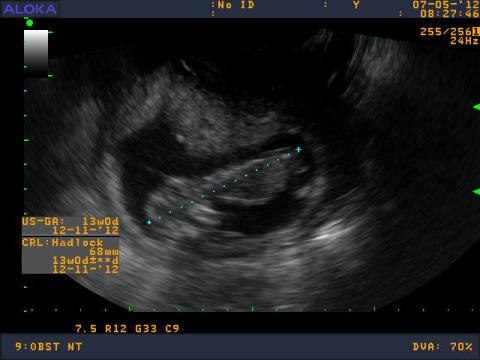

chcela by som sa opytat. Gynekolog mi robil v 13tt vaginalne UTZ - meranie myslim ze sa vola CRL, lekar mi povedal, ze mam zle tkanivo na sonograf, že aby som sa neplašila, niektoré ženy ho maju dobre a niektoré zle, že to nemá vplyv na vyvoj dieťatka ale že malého nieje dobre vidno aj obrazok zo sona je nejasnejší oproti iným bábätkam v gestačnom tyždni 13tt, čiže meranie NT neprebehlo tak ako malo. Do materskej knižky mi napísal nepriaznivá poloha...prítomnosť nosoej kostičky tiež neviem. Vďaka tomu tkanivu, ale pri ukončení sona ma ubezpečil, že je to vitálna gravidita. Videla som špunta ako si tam v brušku robi kotrmelce a kopká. Ako mu bije srdiečko. Je pravda, že ked som bola 3 tyždne dozadu na UTZ srdiečko som lepšie videla ako teraz, dokonca vtedy som jasnejsie videla ručičky a nožičky. Musela som až oči prižmuriť. Možem to tkanivo nejako ovplyvniť? alebo jeto od prírody dané? a ešte otazočka. Mám sa znepokojovať ked nemám vobec to meranie NT vdaka tkanivu? este som zabudla babatko ma 68mm. Dakujem za odpoved. :-)